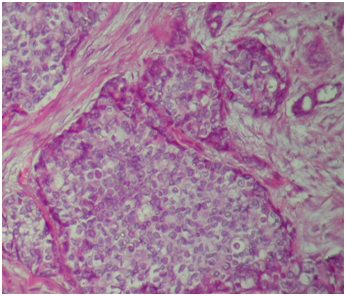

Ten percent neutral buffered formalin was used for fixation and 3 to 5 mm thick representative tissue biopsies were then processed in an automatic tissue processor using SLEE (mtp) processing machine. The blocks prepared by embedding the tissue in paraffin wax, then sectioned at 4μm using micro Tec laborgeräte microtome, and stained with hematoxylin and eosin (Figure 1) for light microscopy. Four sections (4μm in thickness) from each one of sixty biopsies were prepared for histochemical study after dewaxation as follows:

The 60 breast lesions consist of 35/60 (58.3%) malignant tumors and 25/60 (41.7%) benign breast lesions (Table 2). For the 35 malignant samples Immunohistochemically stained for ER, there were 12/35 (34.3%) showed positive expression and 23/35 (65.7%) showed negative expression. From benign samples, there was 8/25 (32%) ER positive (Figure 3B) and 17/25 (68%) ER negative (Figure 3A). Out of the total study subjects, there was 20/60 (33.3%) ER positive as shown in Table 1&2. Regarding VanGieson, there were 53 positive stained samples (Figure 2A), of them 18/53 (34%) ER positive and 35/53 (66%) ER negative. For the 7 VanGieson, negatively stained samples were 2/7 (28.6%) ER positive and 5/7 (71.4%) ER negative. The correlation between collagen fibers and ER status was found to be statistically significant (P-value = 0.000). Masson trichrome resulted in 46 positive stained samples (Figure 2B), of them were 15/46 (32.6%) ER positive and 31/46 (67.4%) ER negative. For the 14 Masson, trichrome negative stained samples were 5/14 (35.7%) ER positive and 9/14 (64.3%) ER negative. The correlation between collagen fibers and ER status was found to be statistically significant (P-value = 0.000). Verhoeff method resulted in 38 positive stained samples (Figure 2C) distributed as 13/38 (34.2%) ER positive and 25/38 (65.8%) ER negative. For the 22 Verhoeff, negatively stained samples were 7/22 (32%) ER positive and 15/22 (68%) ER negative. The correlation between elastic fibers and ER status was found to be statistically significant (P value =0. 039). Silver stained samples exhibited 39 positive samples (Figure 2D) were 13/39 (33.3%) ER positive and 26/39 (66.7%) ER negative. For the remaining 21Silver stained negative samples were 7/21 (33.3%) ER positive and 14/21 (66.7%) ER negative.